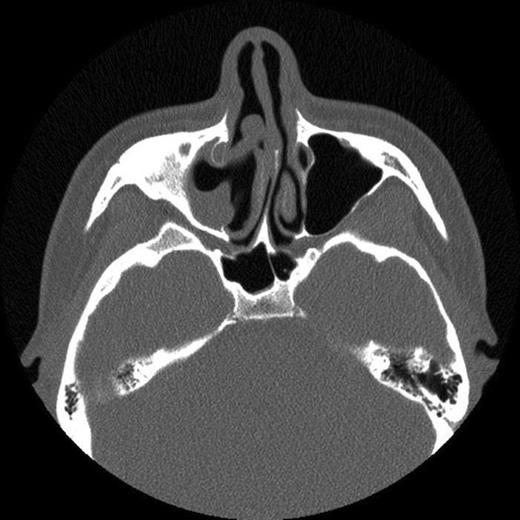

The patient then attended our clinic. Clinical examination and subsequent naso-endoscopy showed evidence of a right sided nasal obstruction with polypoidal mass within the nasal cavity. The patient underwent CT scan sinuses, which showed a well demarcated air defect in the extensively thickened sinus mucosa with large polypoidal mass. Evidence of entry of the cue was seen as a defect in the anterolateral wall of the right maxillary sinus and absent upper medial wall. No FB was seen.

CT scan showing extensive polyp mass in right maxillary sinus with extension into right nasal cavity

The history and CT scan results suggest that following penetration of the snooker cue into the gingivo-labial sulcus it had broken through the right anterolateral maxillary wall and upper medial wall. On withdrawal of the snooker cue, the cue tip had broken off in the maxillary sinus. The FB had then caused localised inflammation resulting in episodes of sinusitis and facial pain. The FB had subsequently been discharged during a coughing episode 12 years later.